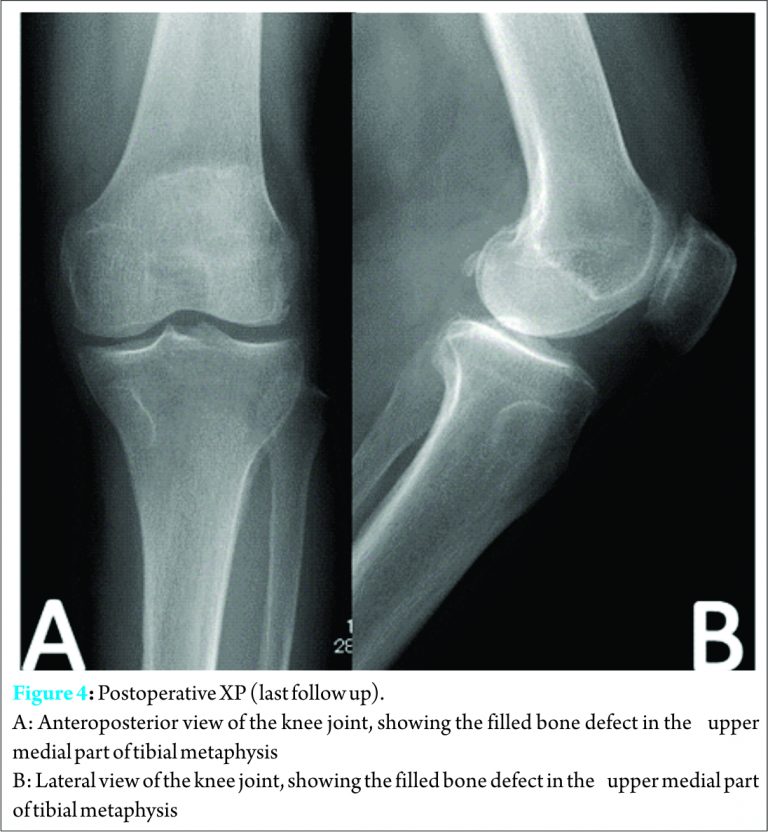

Immunohistochemical stains to SMA were diffusely positive. The surgical margin was free of tumor. Otherwise, the histological exams were compatible with the results of biopsy and confirmed the diagnosis of intraosseous leiomyoma. The patient symptoms had improved after surgery, pain gradually improved postoperatively until it disappeared by two months after surgery, weight bearing was allowed from next postoperative day, convalescence passed uneventfully. At the latest follow-up after 18 months following surgery, the range of motion of left knee achieved full extension and flexion to 130 degrees without discomfort without any instability or residual pain of the knee. No local recurrence, malignant change, or distal metastasis had occurred.